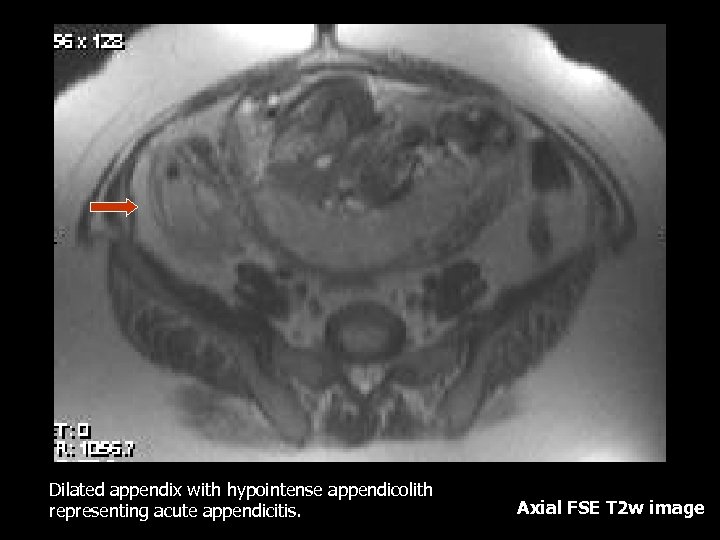

Dilated appendix with hypointense appendicolith representing acute appendicitis. Axial FSE T 2 w image

Appendicitis • Most common non-obstetric surgical condition, also the most delayed due to overlap of symptoms with normal pregnancy(3). • Most reliable symptom is right lower quadrant pain(3). • Leukocytosis may be physiologic since the normal range in a gravid patient may range from 6, 000 to 16, 000(3). • Delay may cause increased fetal and maternal mortality therefore early diagnosis is essential(3).

Appendicitis MRI Findings: • Marked wall enhancement and distention with fatsuppressed, contrast-enhanced T 1 weighted images (2). • However it is possible to make the diagnosis without contrast (2). • T 2 weighted images with fat suppression can show a thickened appendiceal wall, intraluminal fluid and peri -appendiceal inflammation. • Appendicolith will appear as a round signal void in all sequences, however it might be difficult to differentiate from intra-luminal air.